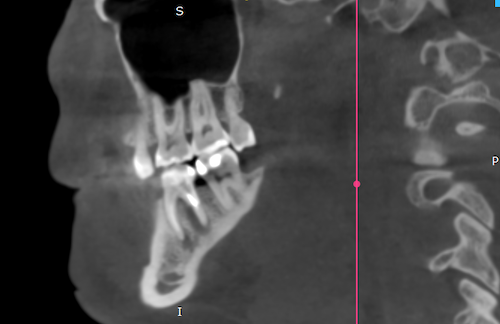

Рис.1 Киста на корнях нижнего 6-го зуба (зона затемнения)

Такие кисты могут появляться и увеличиваться без симптомов боли, и начать давать о себе знать в острой фазе в виде отека, боли при накусывании, повышении температуры и т.д.

В запущенных случаях спасти зуб становится невозможным и его требуется удалить. Оставлять зуб с кистой нельзя. Это приводит к разрушению костной ткани и является очагом хронической инфекции. Такие проблемы с зубами могут приводить к снижению работоспособности, вялости, сонливости, снижению иммунитета организма.